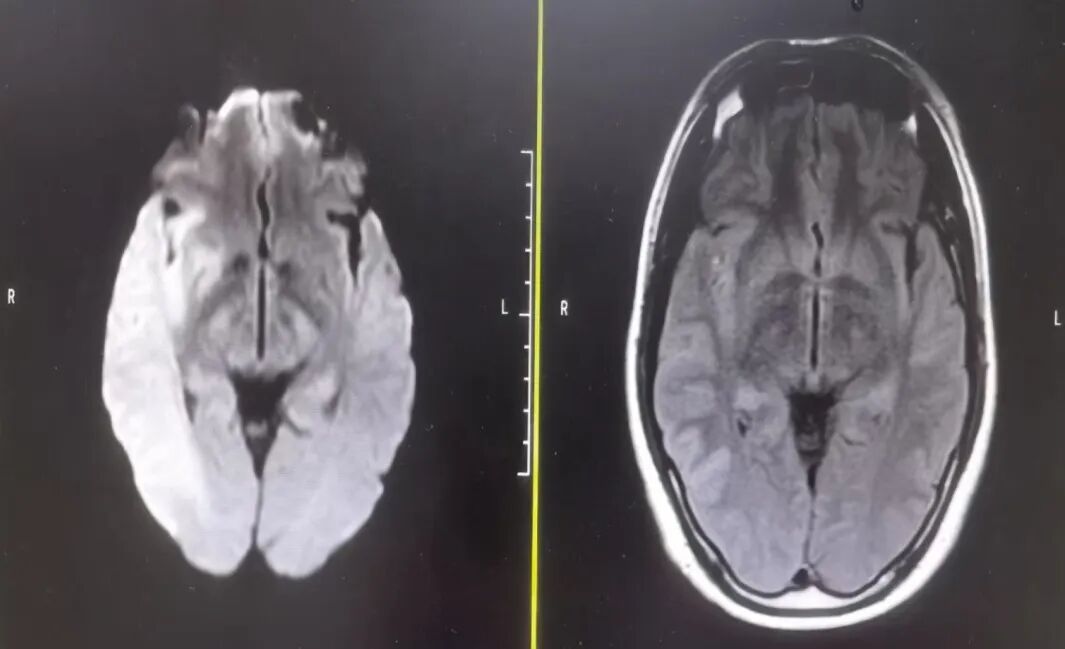

术前头颅DWI+Flair。

动脉长鞘怎么置入有励可说|Locaste 088励楷长鞘在右侧颈内动脉闭塞并夹层术中的应用_https://www.jmylbn.com_新闻资讯_第5张